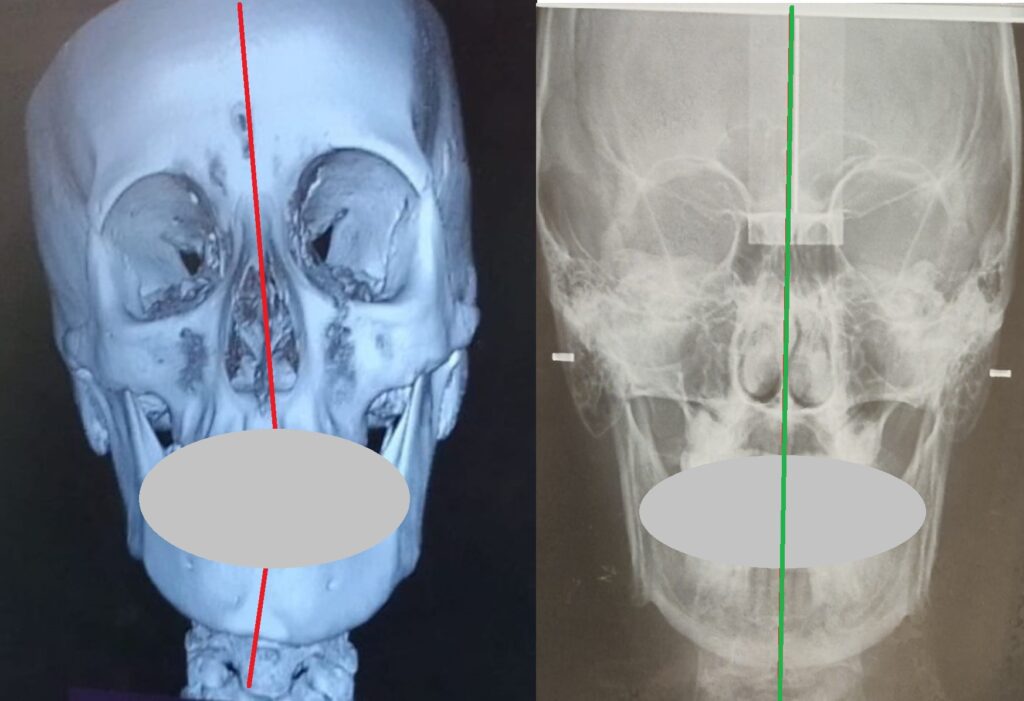

Non prendiamo come riferimento l’immagine di profilo più copiata nel mondo della postura e di certe discipline mediche come l’odontoiatria, la gnatologia e l’osteopatia; prendiamo l’immagine della scoperta OcclusioneGravità® che indica un teschio con rapporto scheletrico a-simmetrico:

Che questo rapporto tra cranio e mandibola non è una condizione patologica ma è la condizione ABITUALE, NORMALE per tutta la popolazione mondiale.

La variabile che rende ogni individuo diverso dall’altro è la differenza tra i gradi di Dis-Equilibrio tra queste parti scheletriche (e conseguentemente articolari e muscolari) e la loro disposizione sui TRE assi spaziali (frontale, longitudinale, sagittale).

Questa è la vista frontale.

Per ragioni di praticità dobbiamo utilizzare un rapporto scheletrico molto evidente come questo:

Il rapporto scheletrico è molto simile all’immagine creata da Formia Maurizio e pubblicata nel suo libro nel 2009, copiata senza citarla in numerosi documenti e riviste scientifiche.

Abbiamo coperto volutamente e provocatoriamente i denti perchè lo scheletro si vede ugualmente non simmetrico anche senza bocca e denti. Si vede anche senza una lastra:

A livello di rx possiamo dire che cranio e mandibola, prima e dopo, sono diventati simmetrici applicando la scoperta del Meccanismo OG. Un evento esclusivo mai visto in tutto il mondo accademico e non, in tutto il pianeta.

I condili della mandibola si riallineano, si riallineano le ossa SUI TRE PIANI SPAZIALI ruotando tra loro e inclinandosi fino ad arrivare ad una posizione di simmetria e di EQUILIBRIO MECCANICO ABITUALE.

Per la rx a destra abbiamo ricevuto complimenti anche da una prestigiosa università italiana che è tra le più prestigiose del mondo.

Il grande paradosso che vogliamo farvi comprendere e che nessuna disciplina, università, centro di ricerca ha voluto approfondire (e comprendere) è che tolte le rx, tolta la “visione” medica del problema che non sta a noi approfondire, non siamo medici e non vogliamo esserlo, è che queste teste pesano dai 5 ai 7 KG e se inclinate di qualche grado a causa del Dis-Equilibrio tendono a cadere come una palla (freccia rossa evidenziata anche nelle immagini precedenti) e possono arrivare a pesare, ai nostri muscoli, anche 25 KG.